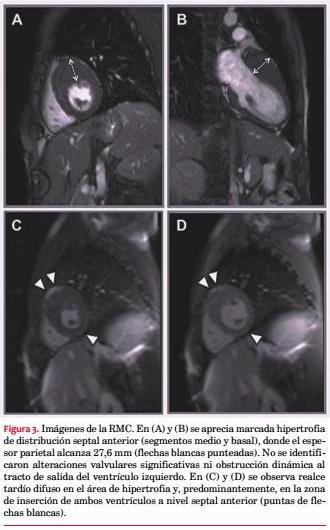

El enfoque terapéutico de la MCH se focaliza en dos grandes objetivos: tratar los síntomas y prevenir la MS. Este último punto obliga a estratificar precozmente el riesgo individual de MS en todos y cada uno los casos. Tradicionalmente, los factores de alto riesgo incluían el grosor parietal máximo >30 mm, la taquicardia ventricular no sostenida, el síncope de causa no aclarada, los antecedentes familiares de MS y la respuesta hipotensora al esfuerzo(1,2). La disponibilidad de algunos scores de riesgo representa un aporte novedoso y de potencial utilidad práctica en la estratificación temprana de la MCH. Estos scores son fácilmente accesibles al lado del paciente, están disponibles en dispositivos portátiles y tienen en cuenta varios factores de riesgo que son integrados como variables continuas y no dicotómicas, lo cual podría graduar mejor su peso individual. Dentro de estos scores destaca el MHC RISK-SCD , un modelo de predicción validado por O’Mahony y colaboradores en un gran estudio de cohortes retrospectivo(18). Esta herramienta permite estimar individualmente el riesgo de MS a cinco años basado en los marcadores tradicionales y en otras variables hasta ahora no consideradas como el gradiente de obstrucción al tracto de salida del VI, las dimensiones de la aurícula izquierda y la edad. El puntaje obtenido por el score estratifica el riesgo individual de MS en tres categorías: bajo (riesgo de MS a los cinco años <4%), moderado (4%-6%) y alto (> 6%). Su uso ha demostrado mejores beneficios en aquellos pacientes con uno o más factores de riesgo clásicos, disminuyendo la tasa de implantes de cardiodesfibrilador automático (DAI) innecesarios, pero mantiene un bajo poder predictivo en la subpoblación de pacientes sin ningún factor de riesgo clásico, en quienes se observa el 30% de las MS. Sin embargo, el MHC RISK-SCD SCORE aún no ha sido validado en pacientes menores de 16 años, deportistas de elite, pacientes sometidos a miectomía ventricular/ablación septal con alcohol o con enfermedades metabólicas infiltrativas. Con base en sus resultados, la más reciente recomendación de la ESC define una indicación de implante de DAI, Clase IIa, nivel de evidencia B, en los pacientes de riesgo elevado(1). En este caso, el MHC RISK-SCD al diagnóstico predijo un riesgo moderado de MS a los cinco años (5,89%), aunque muy cercano al riesgo elevado (figura 4). Razonando con base en los marcadores pronósticos tradicionales(1,2), el riesgo de MS está marcado principalmente por la presencia de síncope de causa no aclarada en un sujeto joven. En este contexto clínico, las guías de la Asociación Americana de Cardiología (2011) señalan que el implante de DAI representaría una alternativa “razonable”(19). En este caso se procedió al implante tras adicionar el riesgo asociado a la edad temprana y la fragmentación del QRS al peso pronóstico moderado (cercano a elevado) sugerido por el score MHC RISK- SCD.Tanto la detección de factores de riesgo adicionales como los aportes pronósticos diferenciales de los nuevos scores versus la consideración exclusiva de los marcadores más tradicionales merecen ser evaluados mediante estudios prospectivos.

Reportamos el caso de un joven con MCH asimétrica anteroseptal que se presentó con síncope y marcadas alteraciones en el ECG, entre las que destaca la fragmentación del complejo QRS, un hallazgo asociado a la presencia de fibrosis miocárdica de potencial valor pronóstico. Estratificamos precozmente el riesgo de MS como moderado, con base en las recomendaciones internacionales y el MHC RISK-SCD SCORE. En este contexto clínico, decidimos proceder al implante de un DAI como medida de prevención primaria razonable. Aun disponiendo de modernas técnicas de imagen y nuevos scores de riesgo confiables al lado del paciente, el perfil evolutivo impredecible de la MCH a menudo dificulta la toma de decisiones terapéuticas.